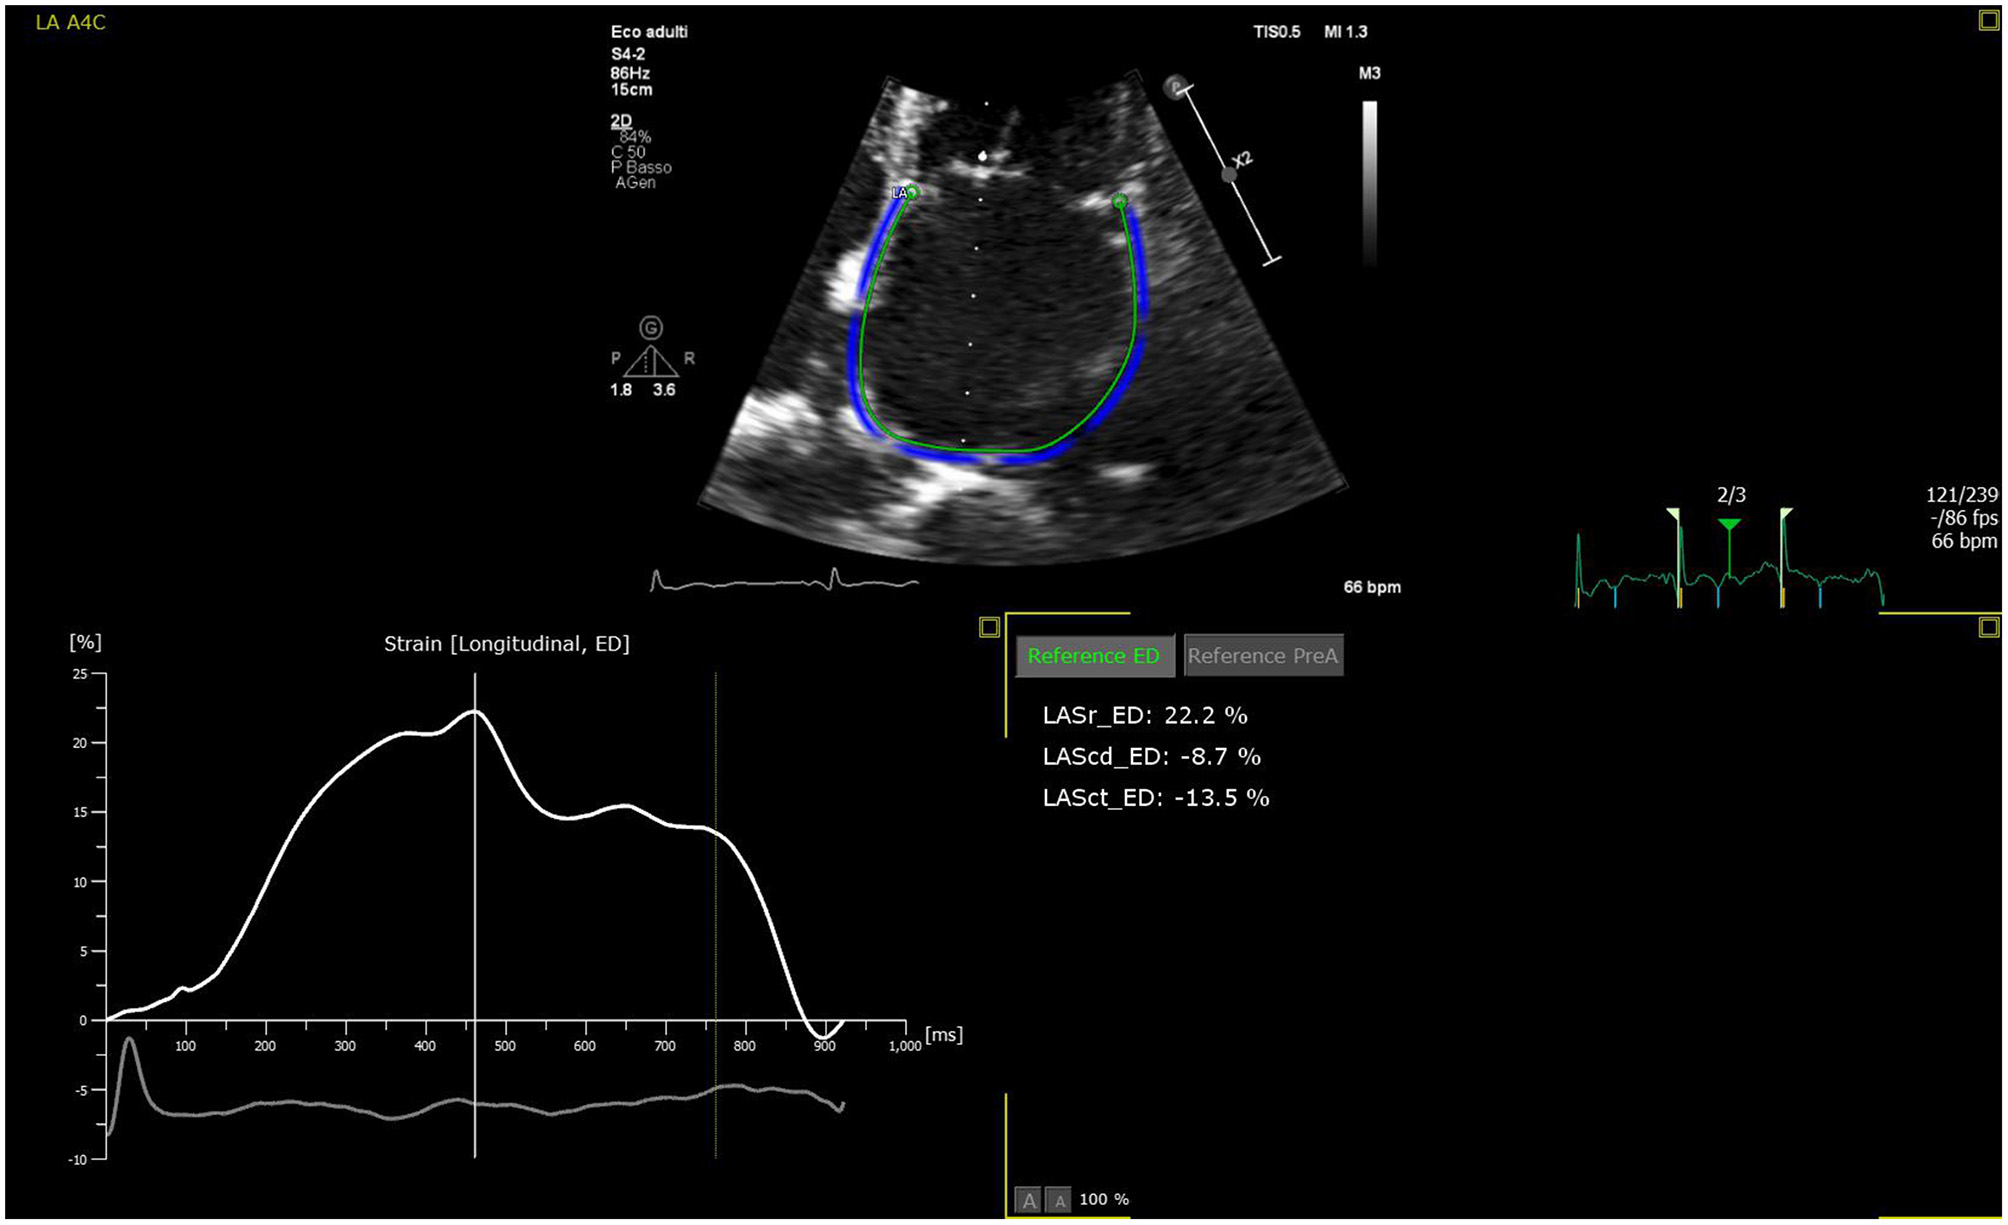

The LA is a dynamic structure, and its mechanical function consists of three phases. It acts as a reservoir of oxygenated blood from the pulmonary veins, and its function depends on both the LV filling pressure and LV end-systolic volume; thus, any LV dysfunction will inevitably impact the atrial reservoir function (12). In early diastole, the LA acts as a conduit between the pulmonary veins and the left ventricle. The compliance of the atrial and ventricular chambers influences the conduit function of the LA, which is mutually related to the reservoir function (13). Usually, this phase makes a minor contribution to ventricular stroke volume but predominates in advanced stages of diastolic dysfunction, when the reservoir function upon atrial contraction is impaired (14, 15). Finally, the atrial booster pump function reflects atrial contractile function. It is dependent on intrinsic LA contractility, the degree of venous return, and LV end-diastolic pressures (16). Growing evidence suggests that the assessment of LA function provides more prognostic information than LA size in HF patients (17). The LA function can be evaluated through 3DE volumetric analysis by measuring all volumes from a single volume trace. Data relative to emptying volumes and fractions can be obtained by assessing the maximum, minimum, and pre-atrial contraction (immediately before) volumes. The transmitral spectral Doppler, pulmonary venous, and left atrial appendix flows also reflect phasic function but are currently rarely used (18). Alternatively, the phasic LA function can be derived from either tissue Doppler imaging (TDI) or 2D speckle-tracking echocardiography (2DSTE) (19, 20). Among these, 2DSTE is the most accurate method due to its ability to analyze myocardial deformation without angle dependency using frame-by-frame tracking of the speckles pattern generated by the interactions between ultrasound and myocardial tissue. The measurement of LA strain depends on whether the P wave (P-LASr) or the QRS (left atrial strain during reservoir phase, QRS-LASr) complex is used as the zero references. However, the recent European Association of Cardiovascular Imaging/American Society of Echocardiography recommends the use of QRS onset as the preferred method (21) mainly due to the impossibility of applying the P wave method to all patients, especially those with atrial fibrillation (AF) (22). The reservoir function is determined by the positive peak of atrial longitudinal strain (PALS), which indicates the LA's maximum elongation during LV systole (23). Hence, PALS also reflects the longitudinal contraction of the LV due to the interdependence between the LA and LV chambers (24). At the end of LA diastasis, there is a progressive shortening of the LA until the first negative peak of atrial contraction strain (PACS) or late diastolic strain. This event reflects the LA booster pump function (Figure 2).

Figure 2

LA strain curve with R-R gating method in apical four-chamber view with zoom-in focus. The patient is an 83-year-old female with chronic heart failure. The patient is in sinus rhythm with reservoir function reduced. Zoomed image is used to increase the frame rate to enhance strain analysis accuracy.